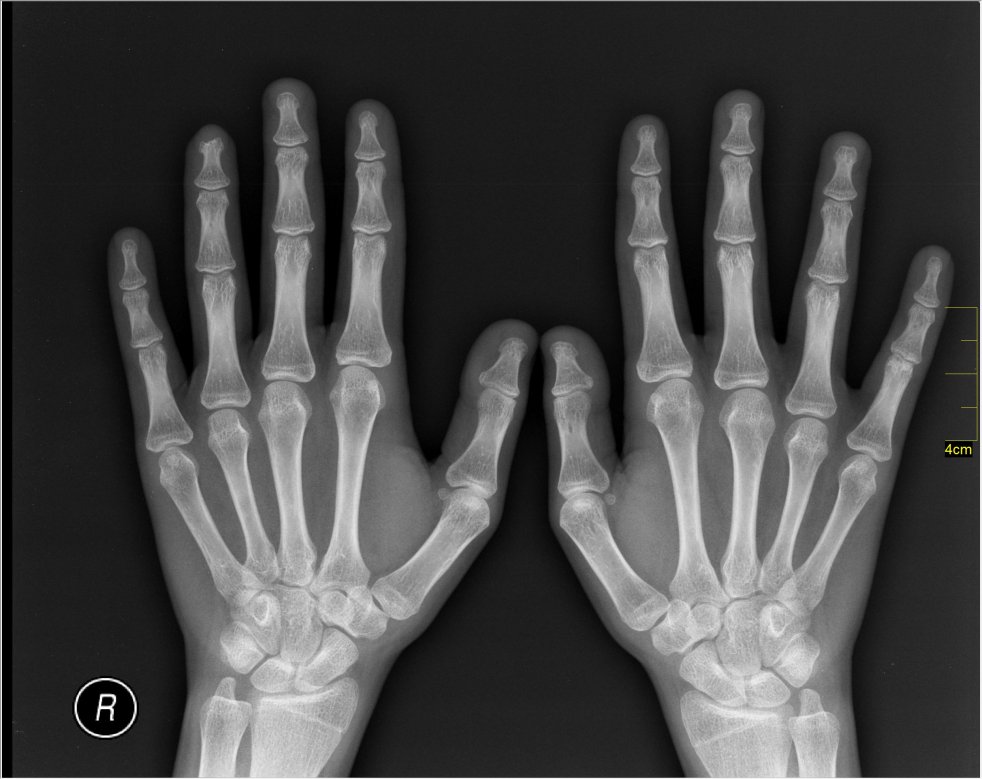

Author Dr. Pierre Bouche, based in the Department of Clinical Neurophysiology, Salpêtrière Hospital, Paris, France, says that in some neuromuscular disorders, carpel tunnel syndrome (CTS) could also manifest during pregnancy.

In the edition Peripheral Nerve Disorders as part of the Handbook of Clinical Neurology, Dr. Bouche states: “[Carpal tunnel syndrome] can develop at any time in pregnancy, but it is most frequent during the third trimester and may be due to fluid retention exerting pressure on the median nerve.” However, this can vary from person to person depending on how sensitive the nerves are around the wrist and upper arm.